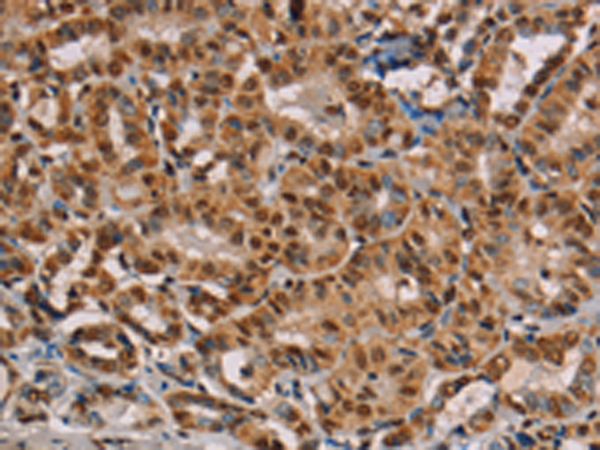

分类: 科研抗体货号: P01426别名: CSA; MOT; MOT2; GRP75; PBP74; GRP-75; HSPA9B; MTHSP75; HEL-S-124m应用: WB,IHC反应种属: Human, Mouse, Rat